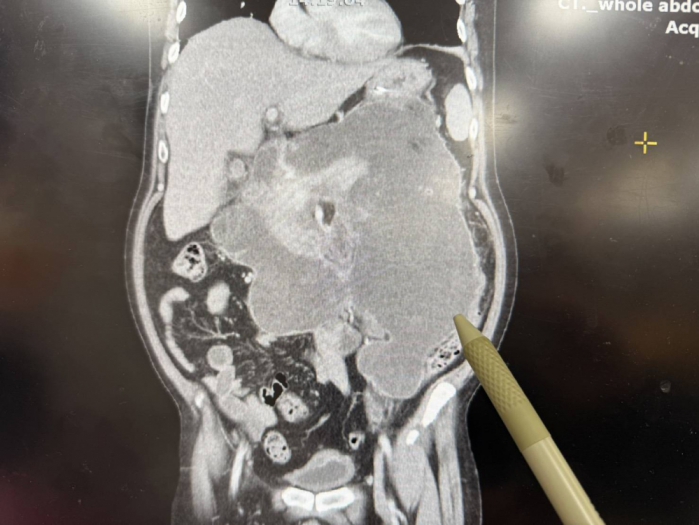

臺中醫院消化外科主任蔡金宏表示,陳先生於去年中因急性胰臟炎住院治療,期間併發十二指腸膿瘍及穿孔,病情相當危急。醫療團隊多次進行清創手術,並採取開放式引流治療,避免膽汁外漏引發急性腹膜炎與敗血症。同時整合開刀房、加護病房、呼吸照護病房、營養科與復健科等跨團隊資源,提供全方位重症照護,才得以讓患者關關難過關關過,預計下週可順利轉出加護病房。

蔡金宏主任指出,胰臟炎合併十二指腸穿孔屬於極嚴重併發症,存活率受多重因素影響。輕度胰臟炎存活率高,但重度胰臟炎死亡率可達四成,若出現嚴重併發症,死亡率甚至高達七成。他強調:「初期正確的治療決策非常關鍵,後續更仰賴重症照護團隊在營養補充與細心照顧上的通力合作,這絕非一人之力可以完成。」